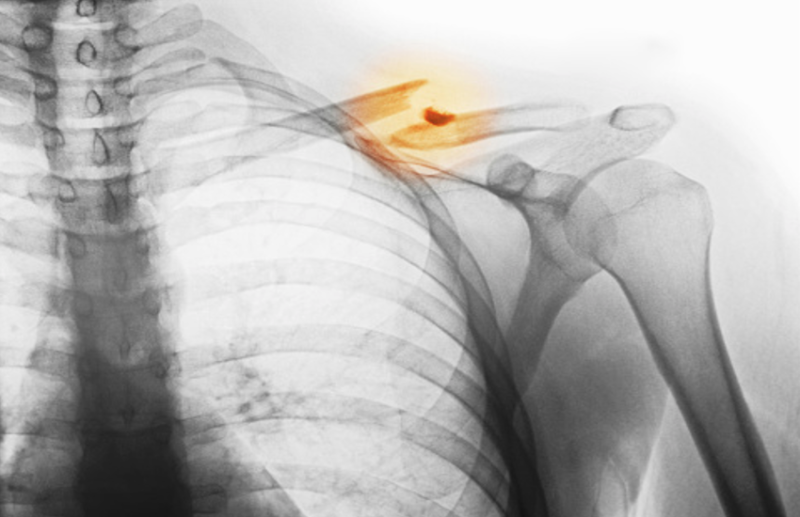

World Osteoporosis Day In Hindi: ऑस्टियोपोरोसिस हड्डी का एक रोग है। जिसमें कैल्शियम की कमी के कारण हड्डियां इतनी कमजोर हो जाती हैं कि वे बुरादे की तरह झड़ने लगती है। इस राेग से पीड़ित मरीज में छीकने से भी फ्रैक्चर होने की आशंका बढ़ जाती है। आज के समय में खराब लाइफस्टाइल व खानपानी के कारण कम उम्र के युवा भी इसकी चपेट में आते देखे जाते हैं। जबकि पहले इस बीमारी के लक्षण 40 वर्ष से अधिक उम्र के लोगों में देखने को मिलते थे। सूचना तकनीक के इस दौर में ऑस्टियोपोरोसिस भयानक रूप धारण करता जा रहा है। एक रिसर्च के अनुसार 50 वर्ष से ज्यादा उम्र की हर तीन में से एक महिला को व 50 वर्ष से ज्यादा उम्र के हर पांच में से एक पुरुष को ऑस्टियोपोरोसिस के कारण फ्रैक्चर की आशंका हाेती है।

ऑस्टियोपोरोसिस तब होता है जब नई हड्डी के गठन और पुरानी हड्डी के पुनरुत्थान के बीच असंतुलन होता है। शरीर पर्याप्त नई हड्डी बनाने में विफल हो सकता है। हड्डी के सामान्य गठन के लिए दो आवश्यक खनिज कैल्शियम और फॉस्फेट हैं। पूरे युवाकाल में, शरीर हड्डियों का उत्पादन करने के लिए इन खनिजों का उपयोग करता है।यदि कैल्शियम का सेवन पर्याप्त नहीं है या यदि शरीर आहार से पर्याप्त कैल्शियम को अवशोषित नहीं करता है, तो हड्डियों का उत्पादन और हड्डी के ऊतकों को नुकसान हो सकता है। इस प्रकार, हड्डियां कमजोर हो सकती हैं, जिसके परिणामस्वरूप नाजुक और भंगुर हड्डियां आसानी से टूट सकती हैं। हड्डियां की कमजाेरी की इस अवस्था काे ऑस्टियोपोरोसिस राेग कहा जाता है।

त्वचा में रुखापन, ऑस्टियोपोरोसिस, हड्डी में बार-बार फ्रैक्चर, ज्यादा कमी से अंगुलियां के सुन्न होने की समस्या, हृदय की धड़कनें असामान्य, शरीर में लगातार थकावट, हाथ और पांव में दर्द रहना, कमर में दर्द की शिकायत होने के लक्षण दिखाई देने लगते हैं।